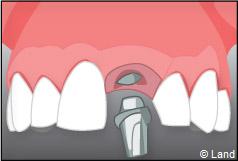

Exemple d’un implant unitaire pour remplacer une dent antérieure manquante.